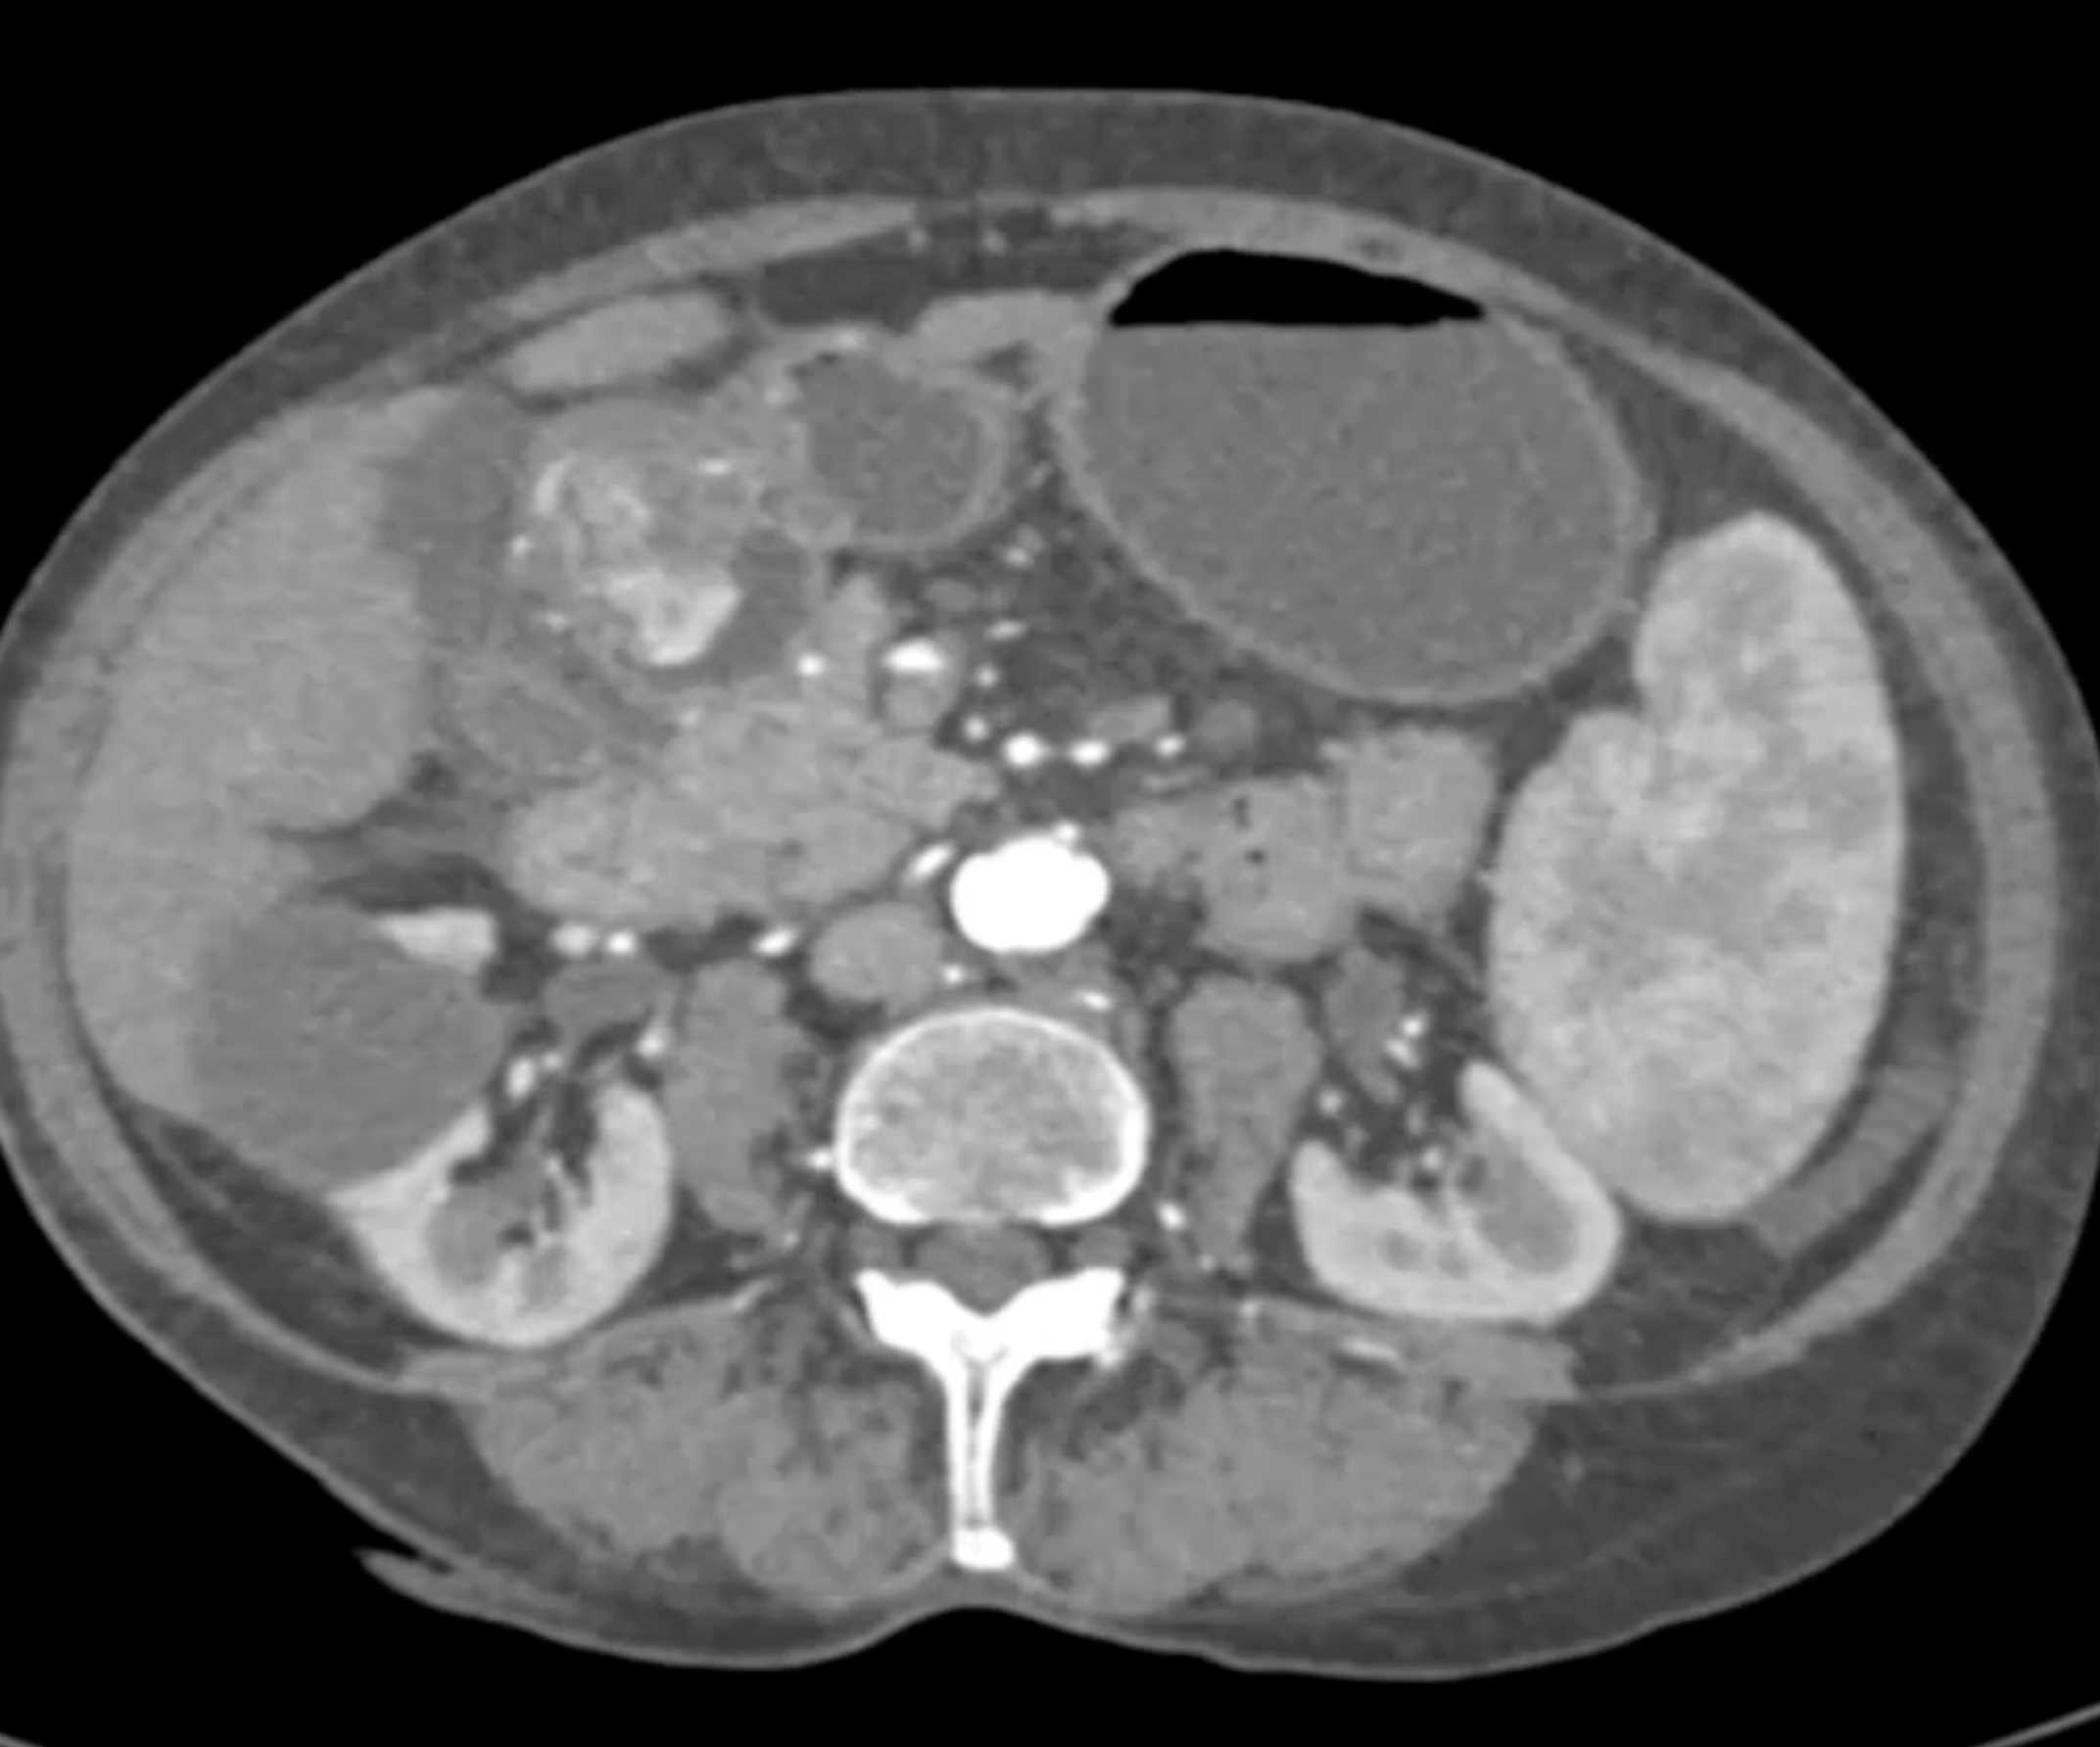

Watermelon Stomach (Gastric Antral Vascular Ectasis)